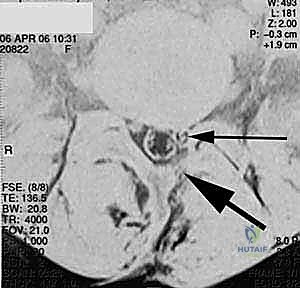

عندما تتآكل هذه الأقراص الغضروفية بسبب التقدم في العمر أو الإصابات، أو عندما تتحرك الفقرات من مكانها الطبيعي، يحدث تضيق في القناة الشوكية أو ضغط مباشر على جذور الأعصاب. هذا الضغط الميكانيكي هو المسبب الرئيسي للألم المبرح الذي يمتد غالبًا إلى الساقين (ما يُعرف بعرق النسا).

- الانزلاق الغضروفي المرتجع أو الشديد (Recurrent Disc Herniation): عندما يبرز الجزء الداخلي الهلامي للقرص الغضروفي ويضغط على العصب بشكل متكرر رغم الجراحات السابقة.

- تضيق القناة الشوكية القطنية (Lumbar Spinal Stenosis): تضيق المساحة التي تمر بها الأعصاب بسبب النتوءات العظمية أو تضخم الأربطة، مما يسبب ألماً شديداً عند المشي أو الوقوف.

في هذه التقنية، يتم الوصول إلى العمود الفقري من الخلف مباشرة. يقوم الجراح بإزالة جزء من العظم (الصفيحة الفقرية Laminectomy) للوصول إلى القناة الشوكية. يتم سحب الأعصاب برفق إلى الجانبين للوصول إلى القرص التالف وإزالته، ثم يتم إدخال "أقفاص" (Cages) مدعومة بطعوم عظمية من كلا الجانبين.

تُعد TLIF تطوراً لتقنية PLIF. بدلاً من الدخول مباشرة من المنتصف وسحب الأعصاب بشكل كبير، يتم الوصول إلى القرص الغضروفي من جانب واحد عبر "الثقبة" (Foramen) - وهي الفتحة التي يخرج منها العصب.

الخطوة 2: إزالة الضغط العصبي (Decompression)

يقوم د. هطيف بإزالة الأجزاء العظمية الضاغطة (Laminectomy أو Facetectomy) والأربطة المتضخمة بدقة ميكروسكوبية لتحرير الأعصاب الشوكية المختنقة.